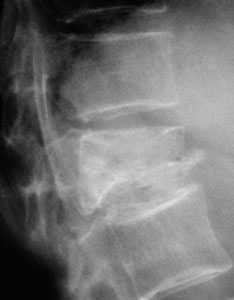

- Π Π΅Π½ΡΠ³Π΅Π½ΠΎΠ³ΡΠ°ΡΠΈΡ ΠΏΠΎΠ·Π²ΠΎΠ½ΠΎΡΠ½ΠΈΠΊΠ°. ΠΠ°Π½Π½Π°Ρ ΠΏΡΠΎΡΠ΅Π΄ΡΡΠ° Π²ΡΠΏΠΎΠ»Π½ΡΠ΅ΡΡΡ ΡΡΠ°Π·Ρ Π² Π΄Π²ΡΡ ΠΏΡΠΎΠ΅ΠΊΡΠΈΡΡ (ΠΏΡΡΠΌΠΎΠΉ ΠΈ Π±ΠΎΠΊΠΎΠ²ΠΎΠΉ) ΠΈ ΠΏΠΎΠ·Π²ΠΎΠ»ΡΠ΅Ρ Π²ΡΡΠ²ΠΈΡΡ ΠΏΠΎΠ²ΡΠ΅ΠΆΠ΄Π΅Π½ΠΈΠ΅ ΠΏΠΎΠ·Π²ΠΎΠ½ΠΊΠ°.

ΠΠΈΠ°Π³Π½ΠΎΡΡΠΈΠΊΠ° ΡΡΠ΅ΠΏΠ΅Π½ΠΈ ΠΏΠ΅ΡΠ΅Π»ΠΎΠΌΠ° ΠΎΡΡΡΠ΅ΡΡΠ²Π»ΡΠ΅ΡΡΡ ΠΏΠΎΡΡΠ΅Π΄ΡΡΠ²ΠΎΠΌ ΡΠ΅Π½ΡΠ³Π΅Π½ΠΎΠ³ΡΠ°ΠΌΠΌΡ.

ΠΡΠ»ΠΈ Π΅ΡΡΡ ΠΏΠ΅ΡΠ΅Π»ΠΎΠΌ, ΡΠΎ Π½Π° ΡΠ΅Π½ΡΠ³Π΅Π½ΠΎΠ³ΡΠ°ΠΌΠΌΠ΅ Π±ΡΠ΄ΡΡ Π²ΠΈΠ΄Π½Ρ:

- ΠΠ»ΠΈΠ½ΠΎΠ²ΠΈΠ΄Π½Π°Ρ Π΄Π΅ΡΠΎΡΠΌΠ°ΡΠΈΡ ΠΏΠΎΠ·Π²ΠΎΠ½ΠΊΠ°.

- Π£Π²Π΅Π»ΠΈΡΠ΅Π½ΠΈΠ΅ ΠΏΡΠΎΠΌΠ΅ΠΆΡΡΠΊΠ° ΠΌΠ΅ΠΆΠ΄Ρ ΠΏΠΎΠ·Π²ΠΎΠ½ΠΊΠ°ΠΌΠΈ.

- ΠΠΎΠ΄Π²ΡΠ²ΠΈΡ Π² ΠΌΠ΅ΠΆΠΏΠΎΠ·Π²ΠΎΠ½ΠΎΡΠ½ΠΎΠΌ ΡΡΡΡΠ°Π²Π΅.

- Π‘ΠΌΠ΅ΡΠ΅Π½ΠΈΠ΅ Π² ΠΏΠΎΠ·Π²ΠΎΠ½ΠΎΡΠ½ΡΠΉ ΠΊΠ°Π½Π°Π» Π·Π°Π΄Π½Π΅Π³ΠΎ ΠΎΡΠ΄Π΅Π»Π° ΠΏΠΎΠ·Π²ΠΎΠ½ΠΊΠ°.

- ΠΠ΅ΡΠΎΡΠΌΠ°ΡΠΈΡ ΠΏΠ΅ΡΠ΅Π΄Π½Π΅ΠΉ ΠΏΠΎΠ²Π΅ΡΡ Π½ΠΎΡΡΠΈ ΠΏΠΎΠ·Π²ΠΎΠ½ΠΊΠ°.